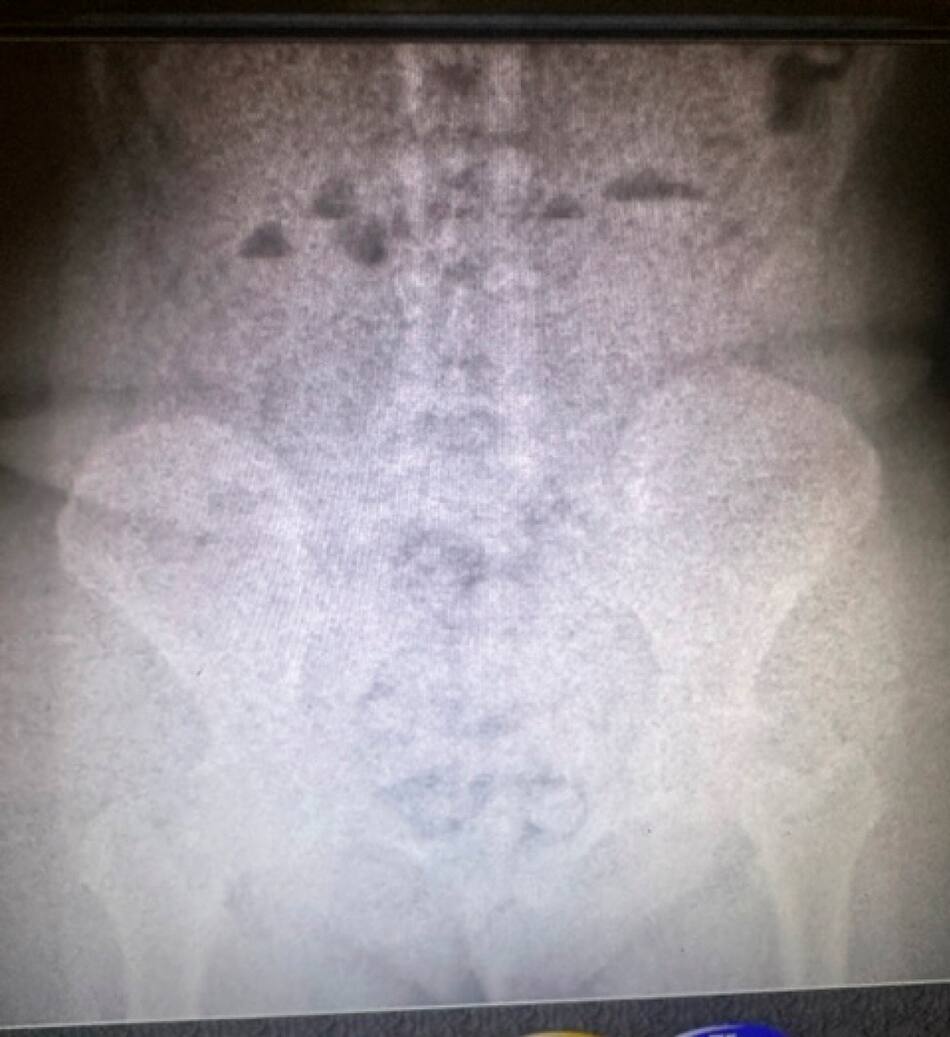

Una primera revisión del equipaje de las mujeres, ambas ciudadanas paraguayas, no arrojó novedades. Sin embargo, con autorización del Juzgado Nacional en lo Penal Económico N°7 —a cargo del Dr. Juan Pedro Galvan Greenway— una requisa personal, junto con un body scan practicado posteriormente —con colaboración de la Policía de Seguridad Aeroportuaria (PSA)—, descubrieron la inequívoca presencia de estupefacientes.

Así, las pasajeras fueron trasladadas al hospital interzonal de Ezeiza, detenidas e incomunicadas, donde, al cabo de su internación, se constató que una de ellas llevaba nada menos que 946 gramos de cocaína en su organismo y la otra, 823 gramos.